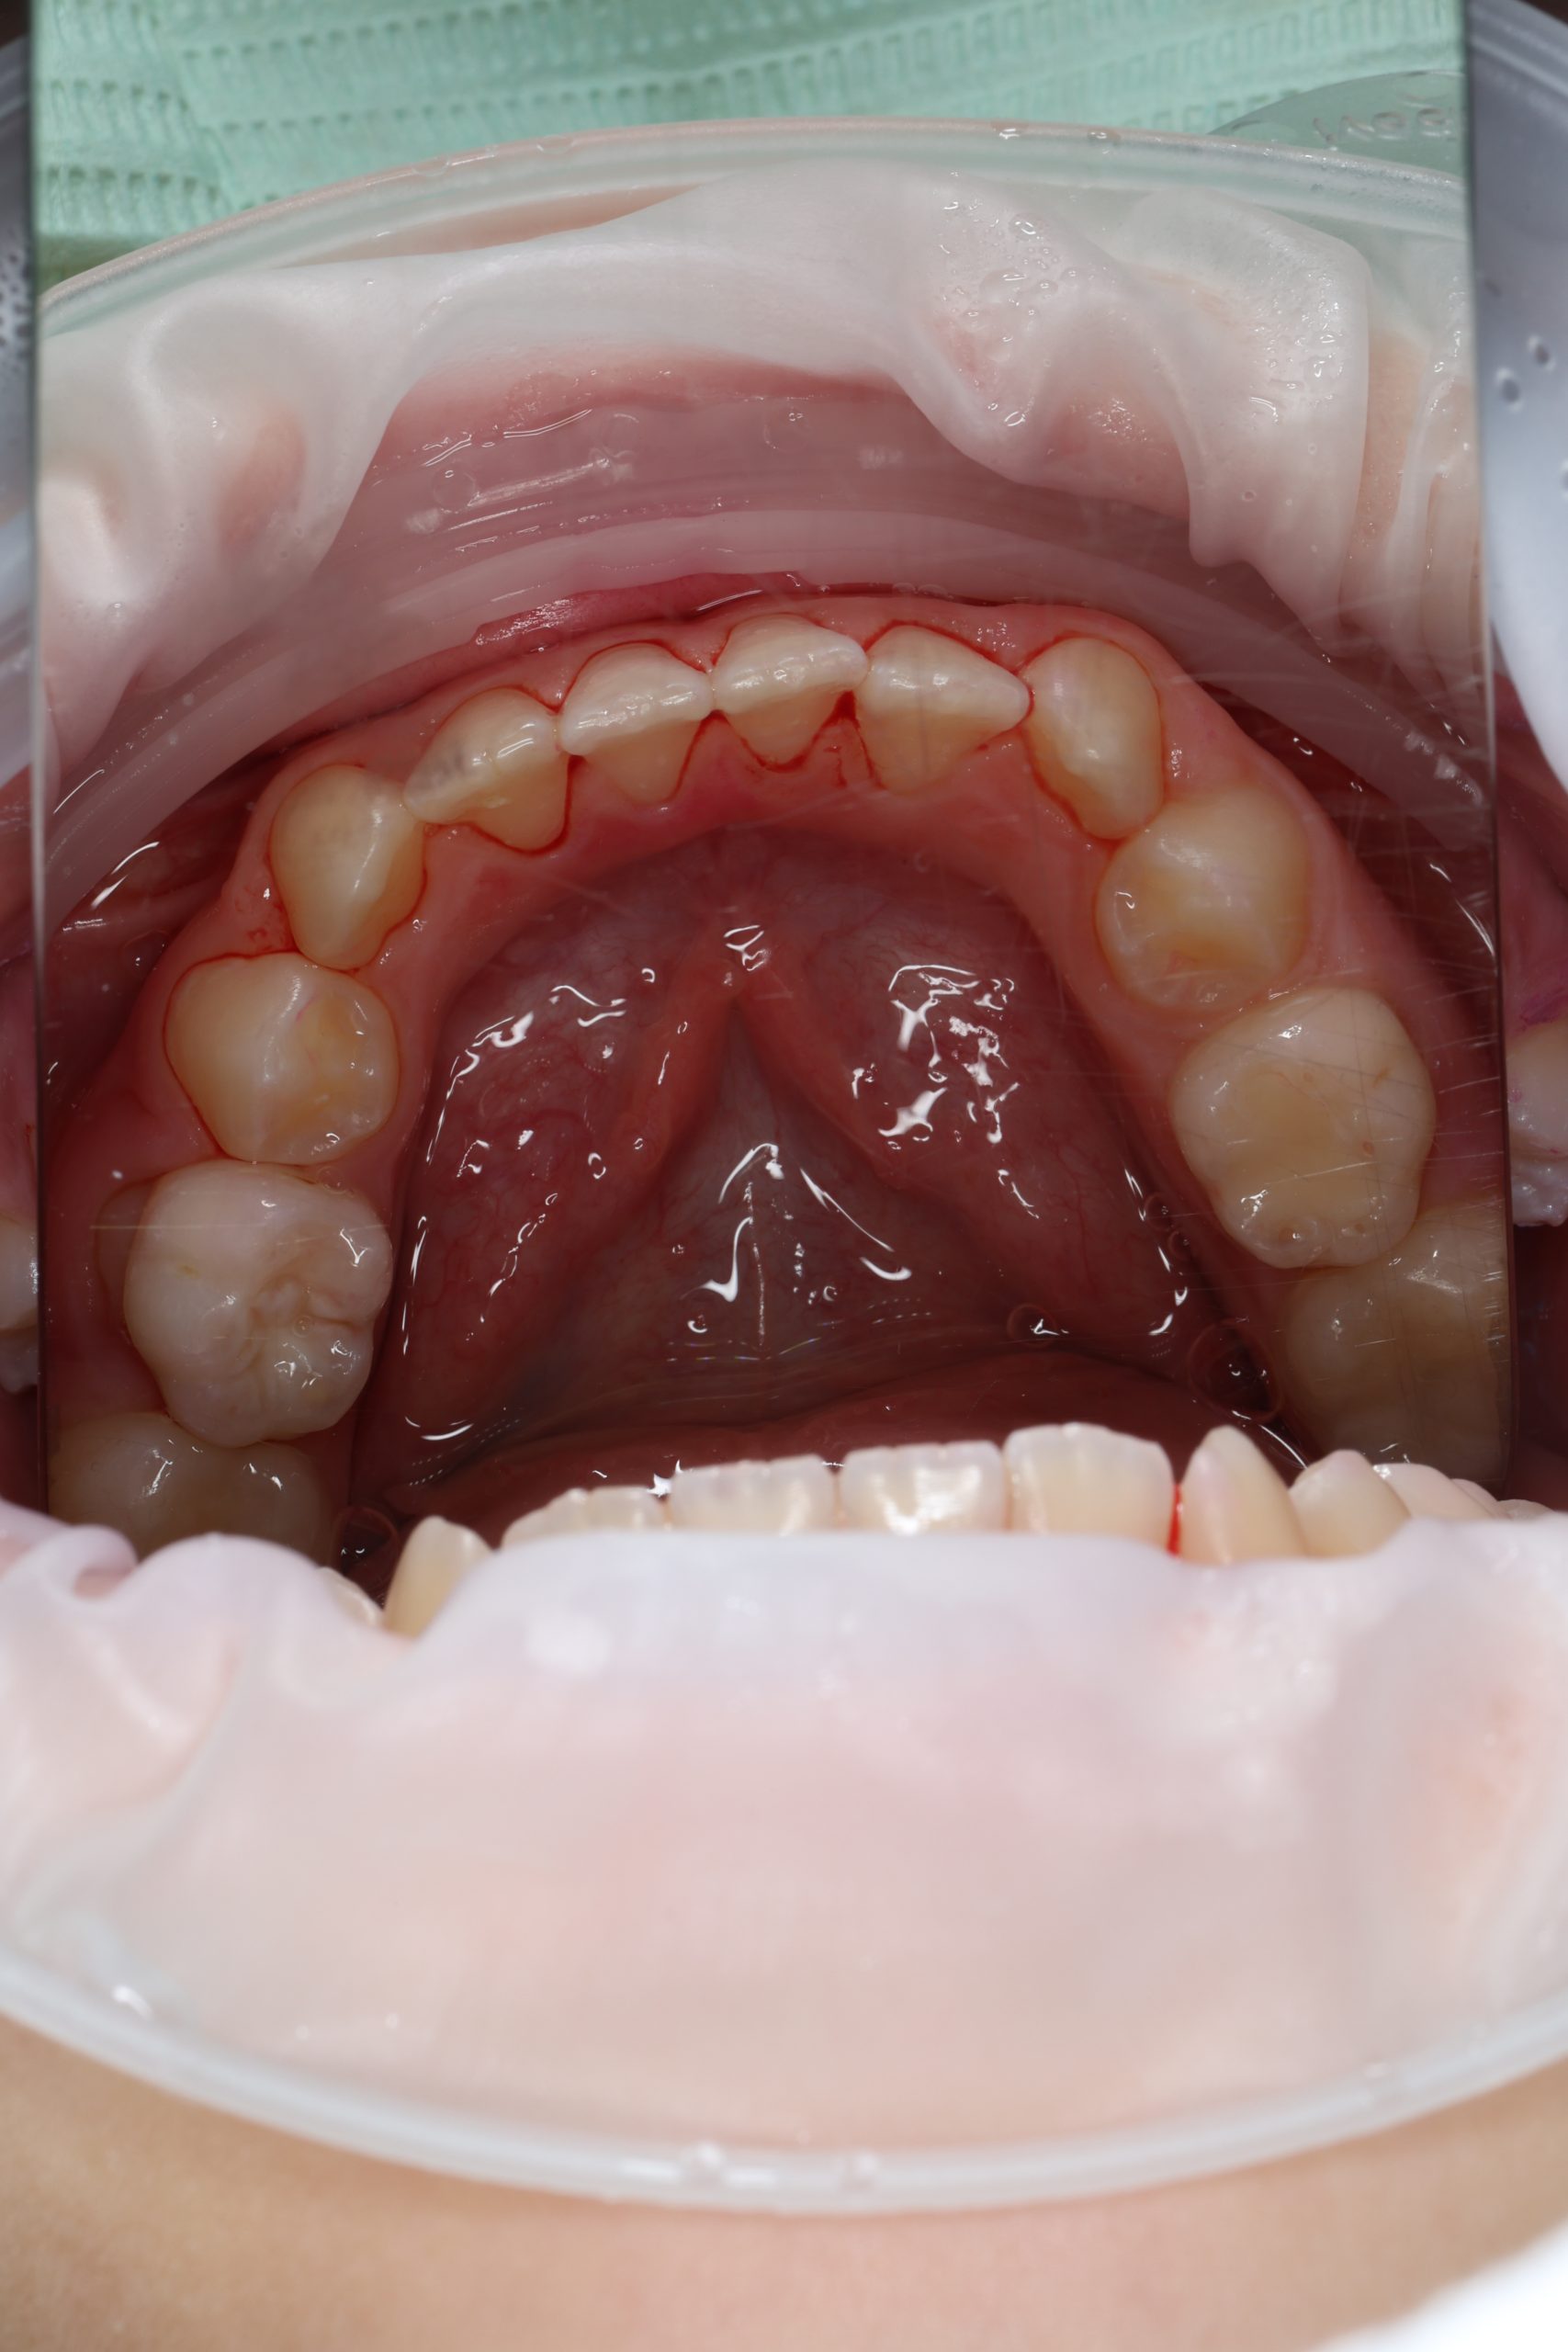

Any tartar is removed gently and painlessly. - Final Check-Up + Fluoride Protection

We ensure the teeth are clean and free from early caries (even in the spot stage), then apply fluoride varnish to protect and strengthen enamel. - Personalized Recall Plan